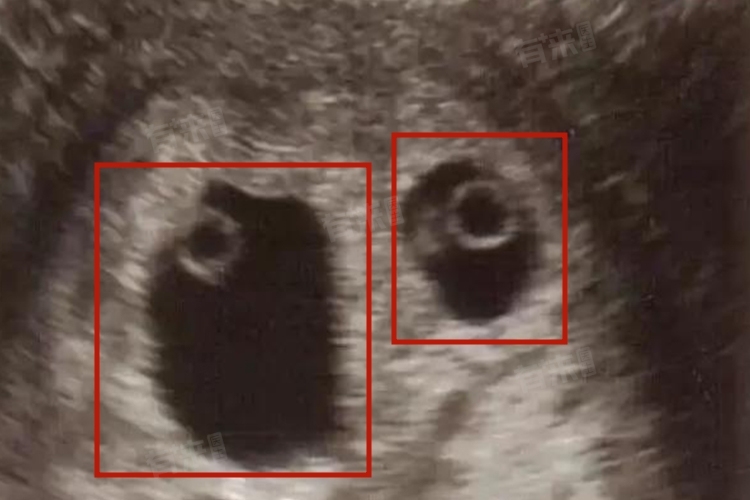

多囊即多囊卵巢综合征,多囊卵巢综合征患者容易怀双胞胎的原因,主要与病理机制导致的生殖内分泌紊乱有关。具体来说,肥胖、家族遗传史、雄激素水平升高等因素可能增加了多囊患者怀双胞胎的几率。

3、雄激素水平升高:多囊卵巢综合征患者体内雄激素水平升高,这可能导致卵泡发育障碍,进而影响排卵和受孕。但是在某些情况下,这种异常的激素环境可能促使卵巢同时释放多个卵子,从而增加了双胞胎或多胞胎的可能性。

4、胰岛素抵抗:胰岛素抵抗是多囊卵巢综合征的常见病理机制之一,会导致卵巢间质产生过多雄激素,从而抑制卵泡成熟和排卵。但在某些情况下,胰岛素抵抗也可能促使卵巢异常排卵,释放多个卵子。